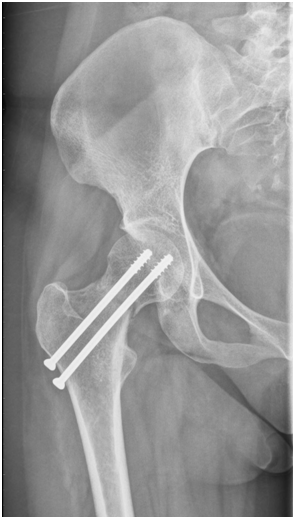

After study protocol patient was treated with surgical reduction and internal fixation with two cannulated screws, recovering diaphyseal cervical angle at 130º (Figure 4), and starts with partial discharge after two weeks of the surgery. Bone callus formation is identified two months after surgery (Figure 5), initiating total support of the limb 3months after surgery, and at 6months he fully reincorporates her activities with excellent clinical evolution. After two years of follow-up on his control radiographs, no avascular necrosis of the femoral head was observed and adequate bone remodeling appreciated (Figure 6).

Figure 4 20/10/2015 pelvic anteroposterior radiograph after surgical reduction and internal fixation with two cannulated screws.